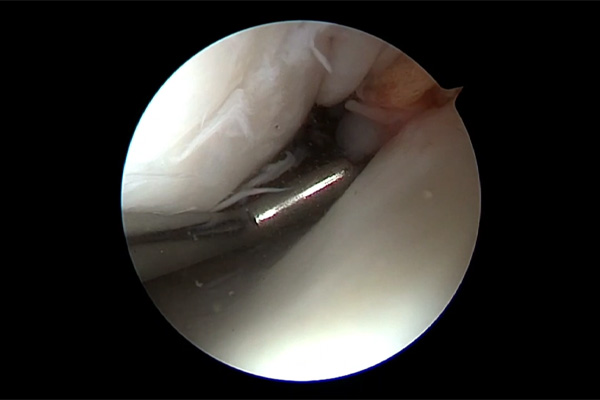

LESIÓN MENISCAL

MENISECTOMÍA PARCIAL MÁS REMODELACIÓN MENISCAL